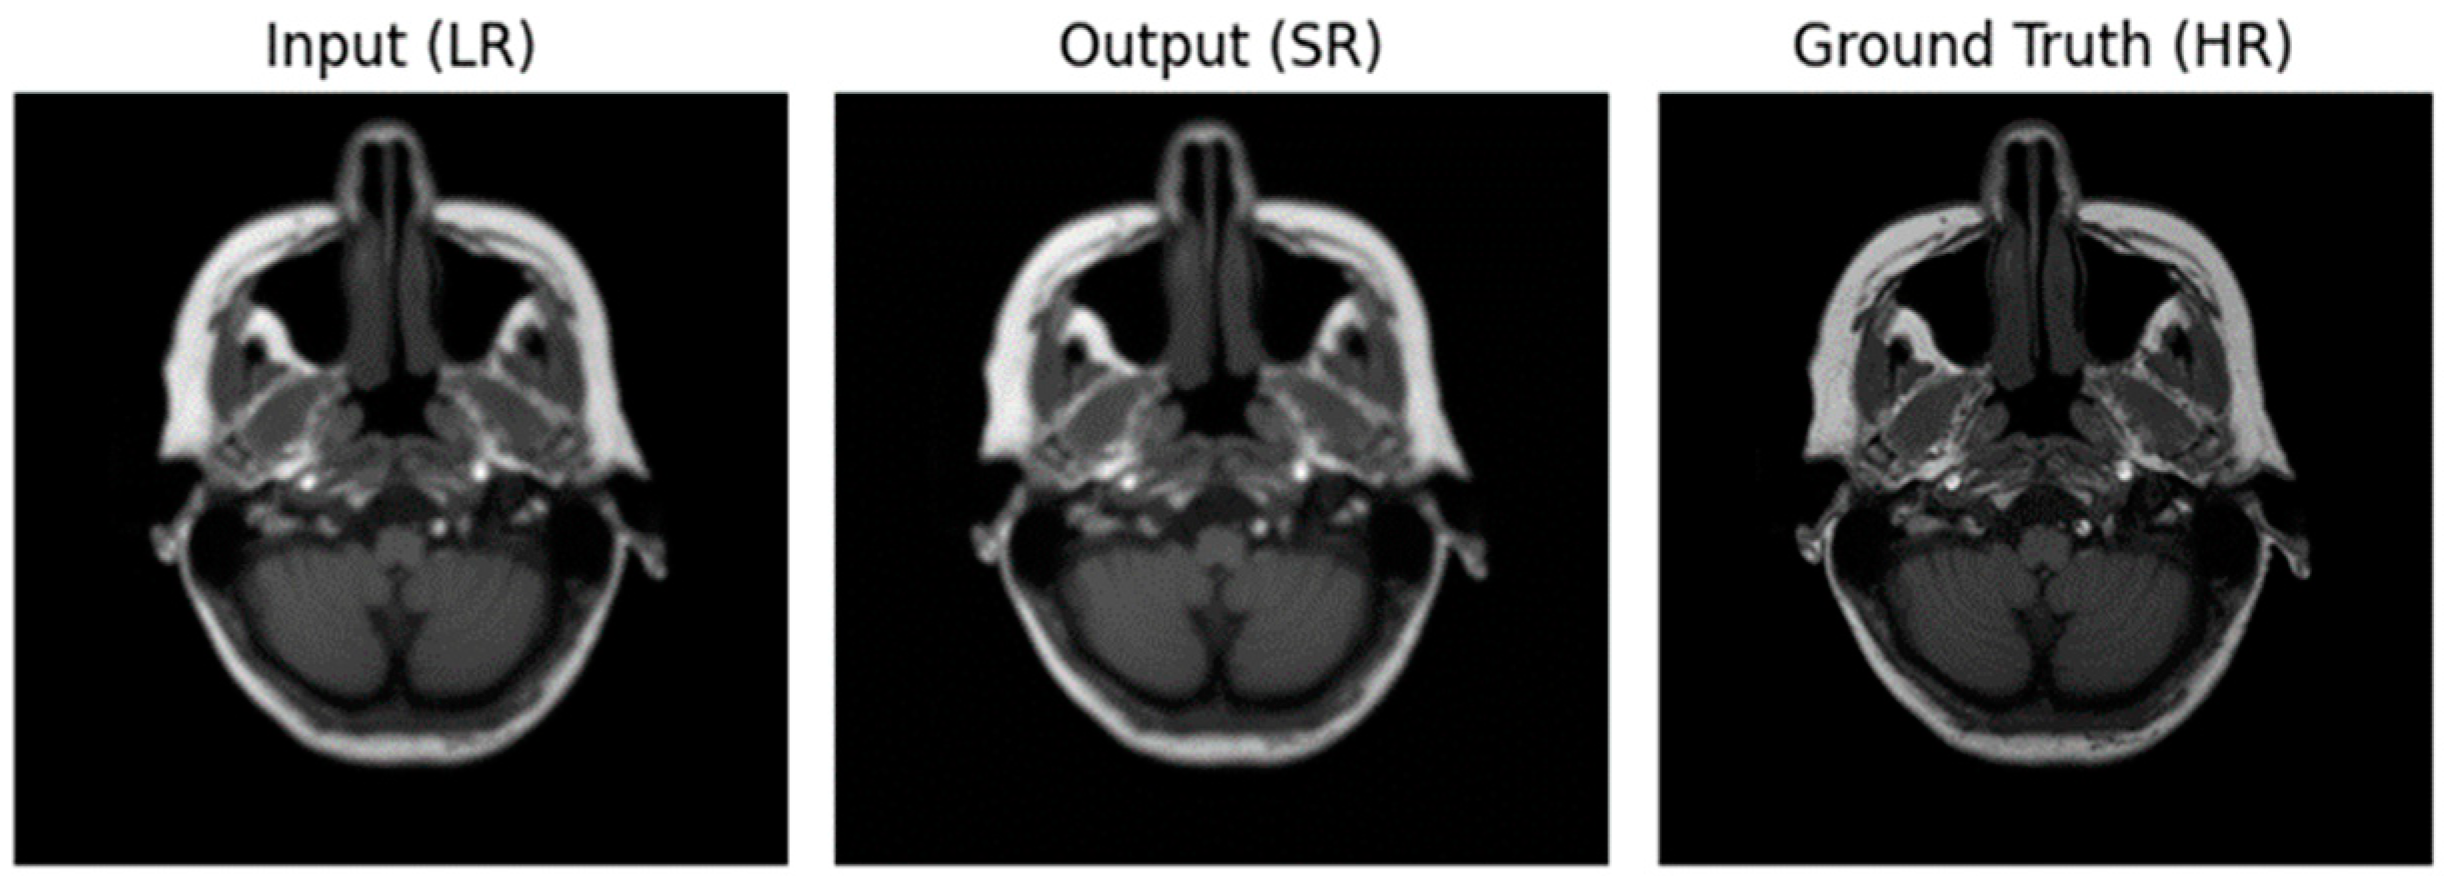

3.2. Performance of ADAM Optimizer and Use of Loss Functions Using Super Resolution Convolution Neural Network (SRCNN)

3.3. Performance of ADAM Optimizer and Use of Loss Functions Using Super Resolution Residual Network (SR ResNet)

3.4. Comparative Analysis Table of SRCNN and SR ResNet with ADAM Optimizer and Loss Functions